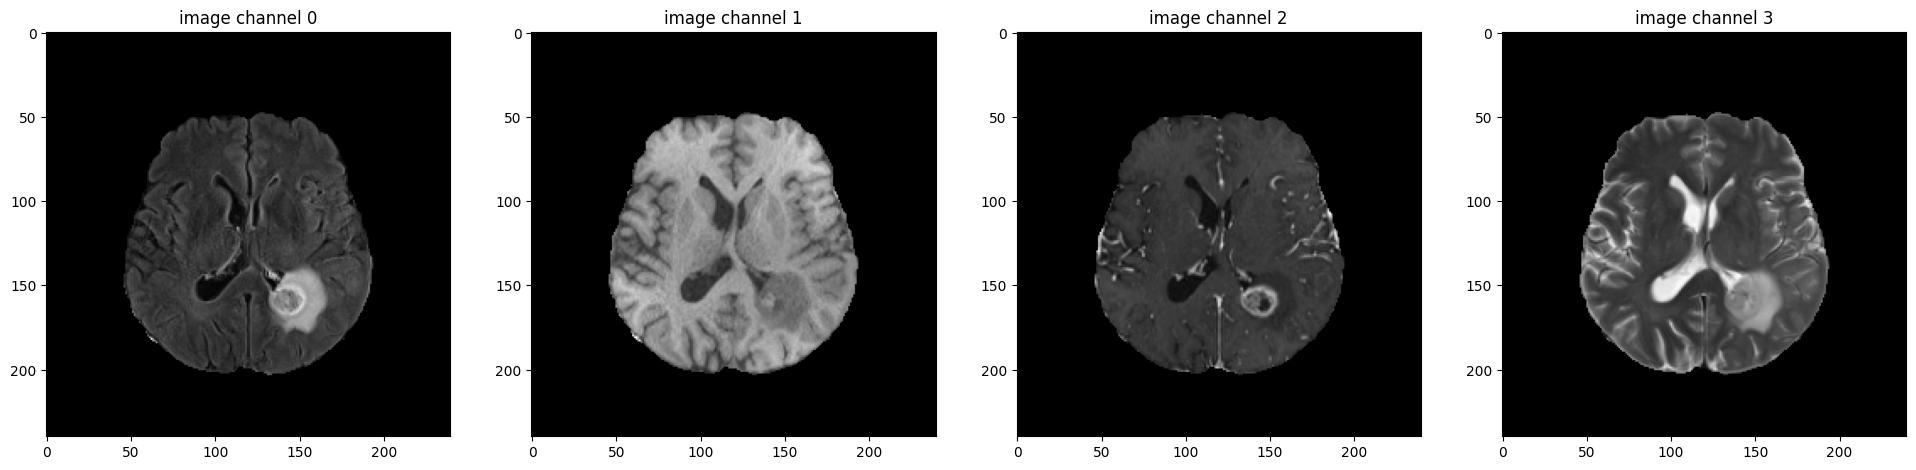

sanity check: Visualize sample image and label channels at middle slice index.

print(f"image shape: {test_image.shape}")

plt.figure("image", (24, 6))

for i in range(4):

plt.subplot(1, 4, i + 1)

plt.title(f"image channel {i}")

plt.imshow(test_image[slice_no, :, :, i], cmap="gray")

plt.show()

image shape: (155, 240, 240, 4)